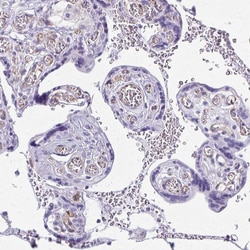

Invitrogen™ NGB Polyclonal Antibody

Immunogen sequence: ESLLYMLEKC LGPAFTPATR AAWSQLYGAV VQAMSRGWDG E Highest antigen sequence identity to the following orthologs: Mouse - 93%, Rat - 95%.

| Immunohistochemistry (Paraffin) | |

| Recombinant protein corresponding to Human NGB. Recombinant protein control fragment (Product #RP-104263). | |